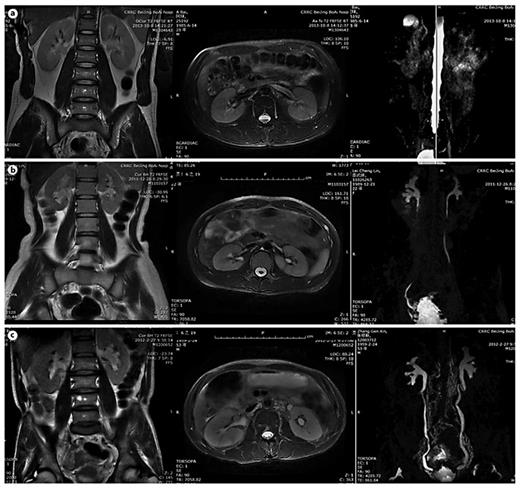

In table 1, LUTD is described according to the Guidelines of the European Association of Urology (EAU) [2] and the terminology of the International Continence Society (ICS) [5]. VUR was graded according to the IRSG, and kidney function was determined by the glomerular filtration rate from isotope renography and the serum level of creatinine. UUTD was graded as follows: grade 0, the central renal complex is closely apposed without UD (fig. 1a); grade 1, slight separation of the central renal complex exists, and the ureter is <7 mm in diameter (fig. 1b); grade 2, the renal pelvis is further dilated, a single or a few calices may be visualized and the ureter is <10 mm in diameter (fig. 1c); grade 3, the renal pelvis is dilated, there are fluid-filled calices throughout the kidney, the renal parenchyma overlying the calices has thinned (renal parenchyma loss <50%), and the ureter is tortuous and <15 mm in diameter (fig. 2a), and grade 4, similar to grade 3, but the renal parenchyma over the calices is thinned (renal parenchyma loss >50%), the ureter is severely tortuous and the ureter is >15 mm in diameter (fig. 2b). For NB patients, detrusor fibrosis and thickening secondary to progressive destruction of the bladder wall often result in ureteral strictures within the bladder wall and distal ureteral obstruction (fig. 2c), which is an important factor in the etiology of UUTD, including HN and UD, and often results in chronic renal failure. Therefore, this new system better discriminates among grade changes in UUT function, can provide objective indicators for UUT function and is an important component of long-term follow-up of conservative and surgical treatment (fig. 3).

MRU UUTD grades 0-2. a Grade 0 UUTD: MRU reveals no separation of the central renal complex of the kidneys and no dilation of the ureters. b Grade 1 UUTD: MRU reveals slight separation of the central renal complex of the kidneys and the ureters are <7 mm in diameter. c Grade 2 UUTD: MRU shows that the renal pelvis of the left kidney is further dilated, a few calices may be visualized and the left ureter is <10 mm in diameter.